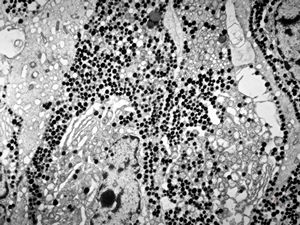

F, 71y. | carcinoid … metastasis to lymphonode